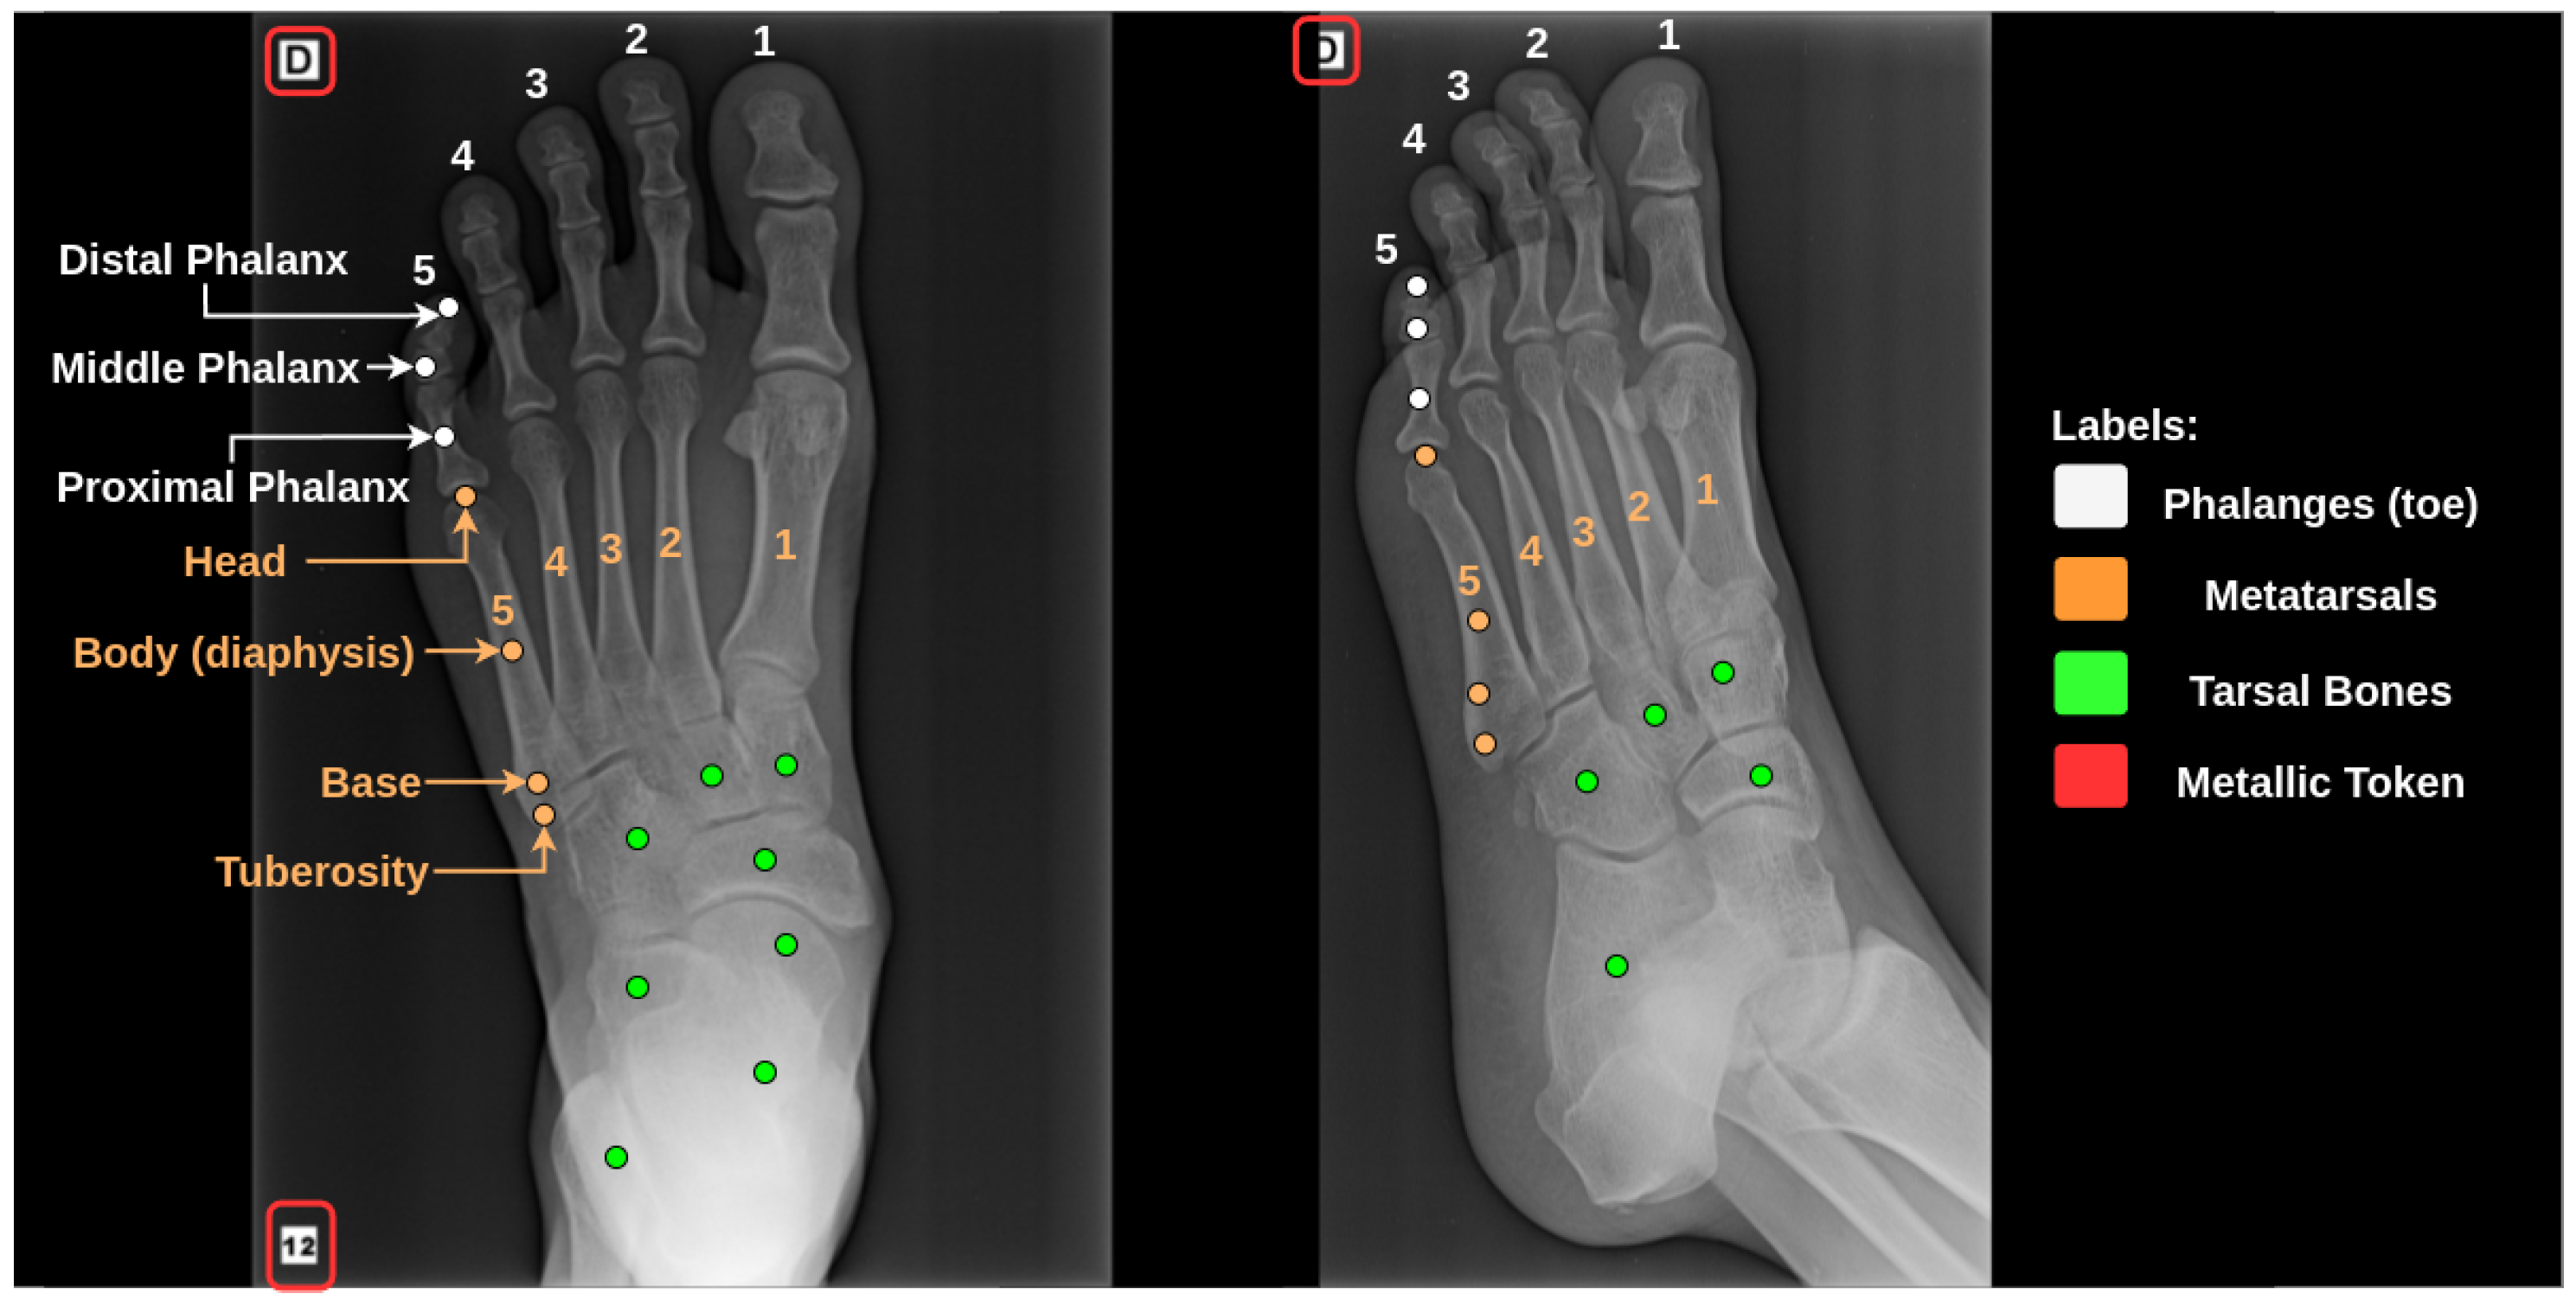

This dataset was collected from hospitals and clinics in all regions of Brazil (North, Northeast, Central-West, Southeast, and South), providing heterogeneity and a wide variety of resolutions, angles, genders, and age ranges, totaling 16,710 exam samples with images and anonymous reports. The exams were obtained in DICOM format and converted to “.png” format for subsequent processing. The images have the Photometric attribute with the Monochrome2 parameter, where higher intensity pixels represent light colors and lower intensity pixels represent dark colors. Figure 3 shows examples of frontal and lateral view images from the same exam. Each view provides specific information about the patient’s condition. For exam labeling, we used the Radiologist Report Interpretation (RIR) methodology [36,37], where specialists analyze the medical reports and classify them according to their content. This methodology was used for all normal class exams and part of the abnormal exams.

The dataset employed in this investigation is derived from multiple sources, generated by disparate equipment and technicians, culminating in images with distinct attributes such as size, contrast, brightness, and framing. To enhance the learning process of the proposed methodology, we have instituted a preprocessing phase aimed at standardizing certain characteristics of the radiographs. Figure 8 delineates the effects of this preprocessing on the original images in both incidences, demonstrating the transformation of the raw data into a more uniform and analyzable format. This rigorous approach ensures the robustness of our method against variations inherent in the data-collection process, thereby increasing the reliability and reproducibility of our results.

The implemented preprocessing protocol encompasses three crucial phases: (1) utilization of the Otsu threshold [38] for the elimination of the peripheral region, preserving only the region of interest with pertinent data; (2) application of zero-padding for the conversion of the image proportions into a square shape, centralizing the image and preventing distortions during the resizing to the standard input dimensions of the CNN used (299 × 299); (3) employment of U-Net for the segmentation of tokens, followed by the application of the Fast Marching Method (FMM) [39] to fill the segmented region. Figure 8 illustrates the results of these phases for both frontal and lateral incidences (As shown in Figure 8, the frontal view contained a metallic token, resulting in the generation of a segmentation mask by U-Net. In contrast, the lateral view did not have the token, leading to the absence of a segmentation mask generated by U-Net).

In the radiograph-acquisition process, metallic tokens containing institutional and patient metadata are frequently incorporated into the final image, as exemplified in Figure 3. These tokens, as indicated by [20,40,41], can engender bias in CNN learning. To address this, we employed U-Net for token segmentation, leveraging its proven generalizability in complex medical imaging scenarios with limited samples [42]. The efficacy of U-Net, demonstrated by an accuracy of 0.991, a Dice index of 0.902, and a Jaccard index of 0.806 in a study by [20], validates its application in our dataset, characterized by diverse token attributes.